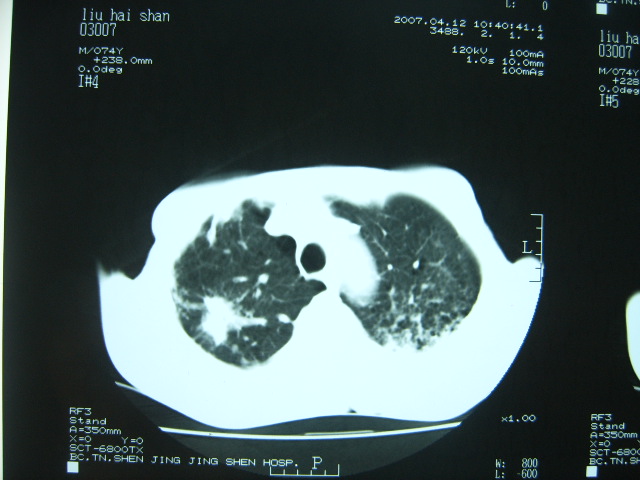

男74岁,咳嗽,寒战,低烧。有糖尿病史。

考虑:1、左下肺脓肿;

2、双肺结核。

考虑:糖尿病合并:1、左下肺炎继发肺脓肿;

两肺结核,左下肺大片实变,内见空洞性病变,壁不规则,结合糖尿病史,考虑:结核性?霉菌性?建议结合实验室检查或治疗后复查。